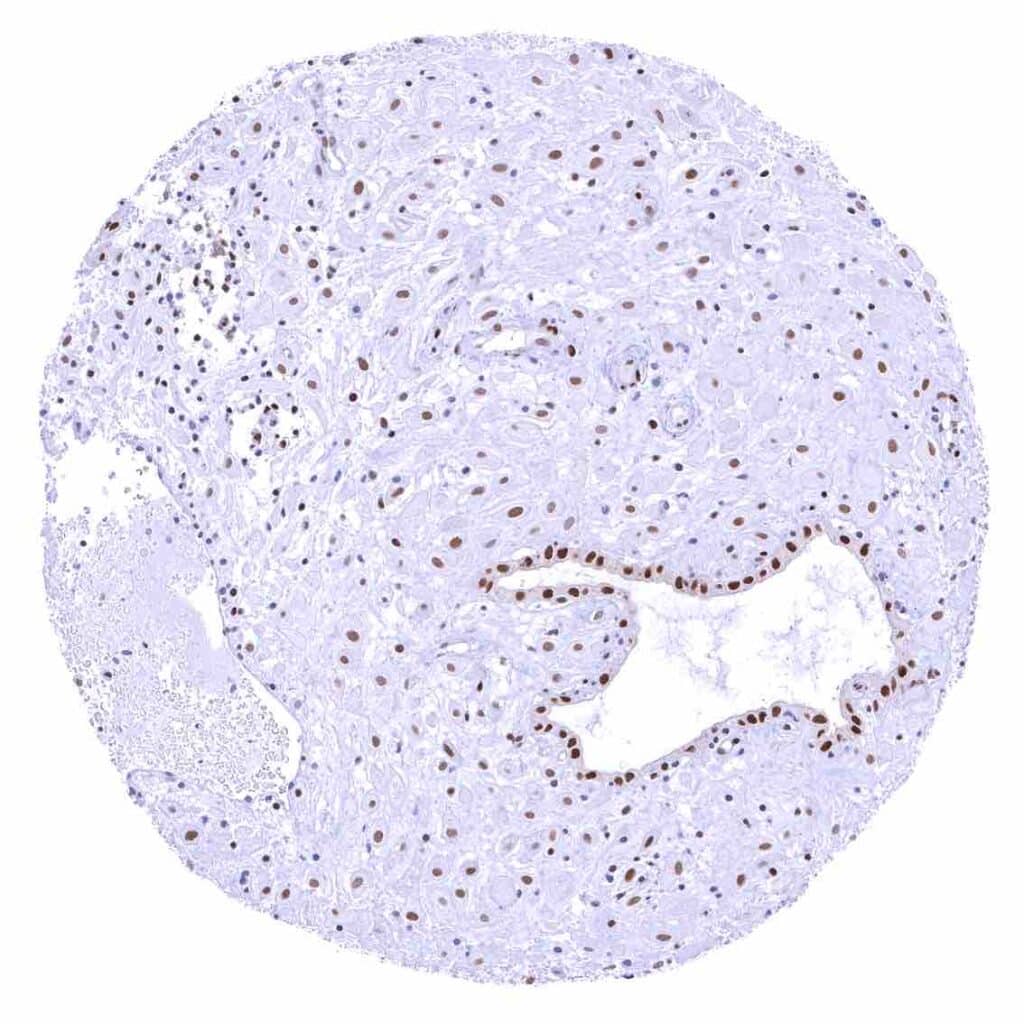

Prostate